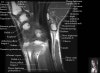

- Axial section

Axial T1 evaluates the tendons of the wrist and carpal tunnel, including the flexor retinaculum.

Axial PD fat suppressed evaluates the tendons of the wrist and carpal tunnel, including the median nerve.